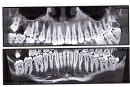

Через 2 недели мне предстоит резекция трех зубов (13,14 и 15) и удаление кисты, в челюстно-лицевой хирургии. Перед резекцией зубы нужно обязательно запломбировать.

Скажите, пожалуйста, есть ли разница, чем пломбировать каналы перед резекцией? И какой материал лучше?